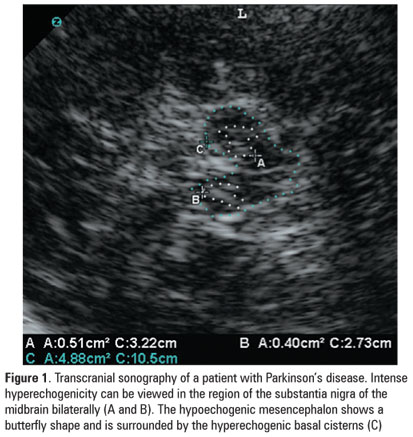

Transcranial sonography has become a useful tool in the differential diagnosis of parkinsonian syndromes. This is a non-invasive, low cost procedure. The main finding on transcranial sonography in patients with idiopathic Parkinson’s disease is an increased echogenicity of the mesencephalic substantia nigra region. This hyperechogenicity is present in more than 90% of cases, and reflects a dysfunction in the dopaminergic nigrostriatal pathway. This study discussed how the hyperechogenicity of the substantia nigra may facilitate the differential diagnosis of parkinsonian syndromes.